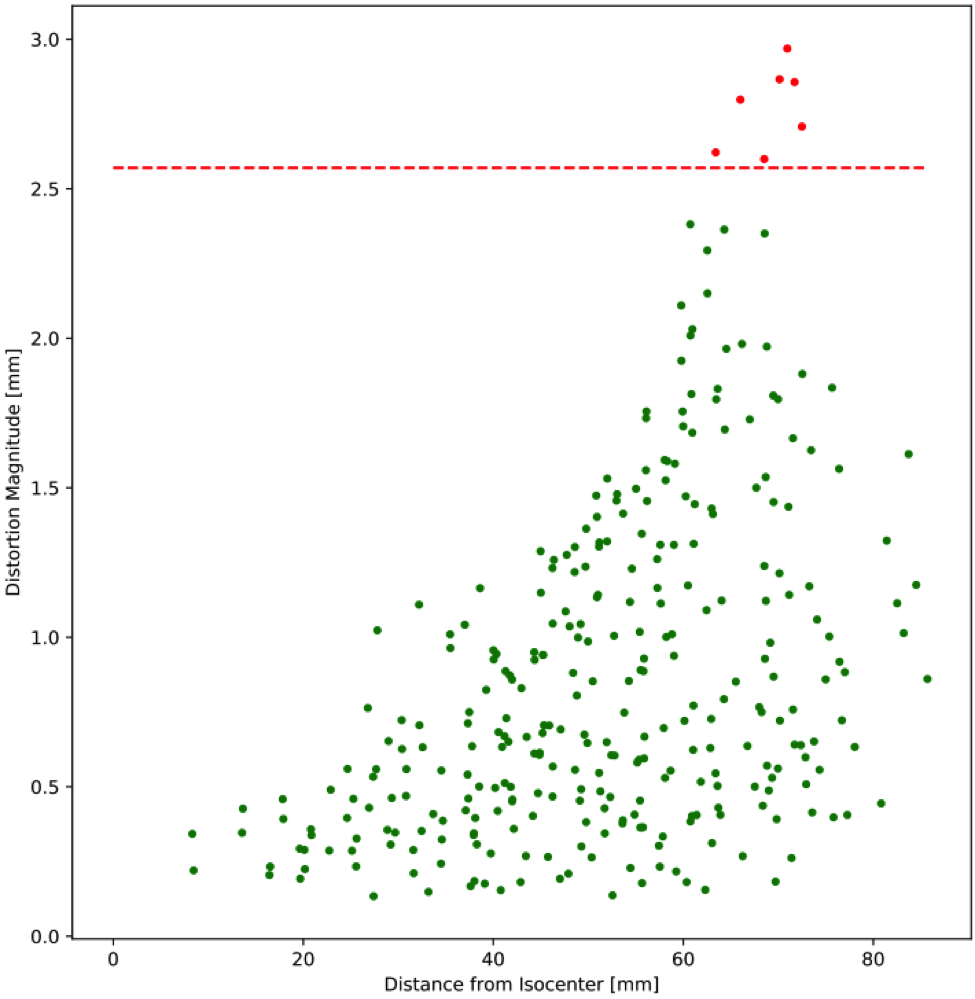

The software registers either a ground truth CAD or CT scan to the detected control points. An interpolation is then performed to generate the 3D distortion vector fields.

Results can be reported in a variety of output formats including scatter plots, contour plots, box and whisker plots for trending, and DICOM overlays that can be exported to third-party software

- Establish distortion tolerance thresholds specific to different imaging sequences